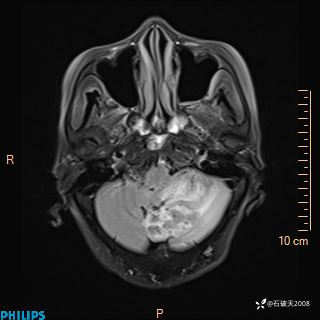

女 86岁 主 诉:乏力1月

现病史:患者1月前活动出现双下肢乏力,无头晕、头痛、恶心、呕吐、肢体活动不利,休息后缓解,间断断发作,症状进行性加重,在家口服药物治疗(具体不详),效差,为进一步诊治,来我院,门诊按“乏力”收住我科,患者自发病以来,神志清,精神稍差,饮食睡眠欠佳,大小便正常,体重未见明显改变。

FLAIR

DWI